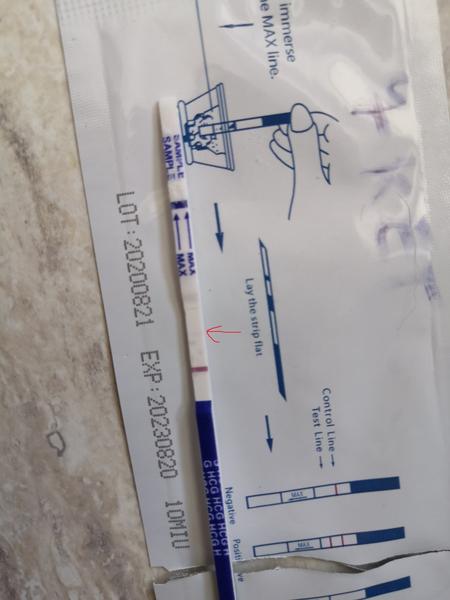

@lenja227 nie nie, nemusi. ani na 10 deň nemusí byť. všetko záleží aj od toho, ktorý deň po KET nastalo uhniezdenie. mne napríklad doktorka povedala, že to môže byť až do 7 dní od KET, a potom jasne, že na 6 deň nebude žiadna čiarka. mne sa na tom tvojom teste tam zdá, že tam je a to ja som väčšinou fakt že slepá, všetci píšu že vidia a ja nevidím nič.

Baby ste fakt zlaté, takáto podpora je super vec a dáva mi to nádej 🙏🙏 dám dva dni pauzu do stredy od testovania, a potom skúsim testom Baby Top Test taky fialový tiež prúžkový.